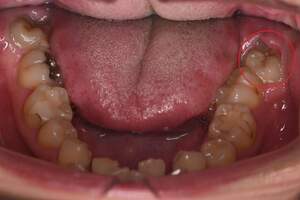

左下の歯茎が腫れている親知らずの症例

- 抜歯前写真(レントゲン、CT等)

左下の親知らず周囲歯肉が腫れていました。

また、手前の歯との間で虫歯もできていました。

口腔内

- Before

- After

半埋伏の親知らずでした。3糸縫合しました。